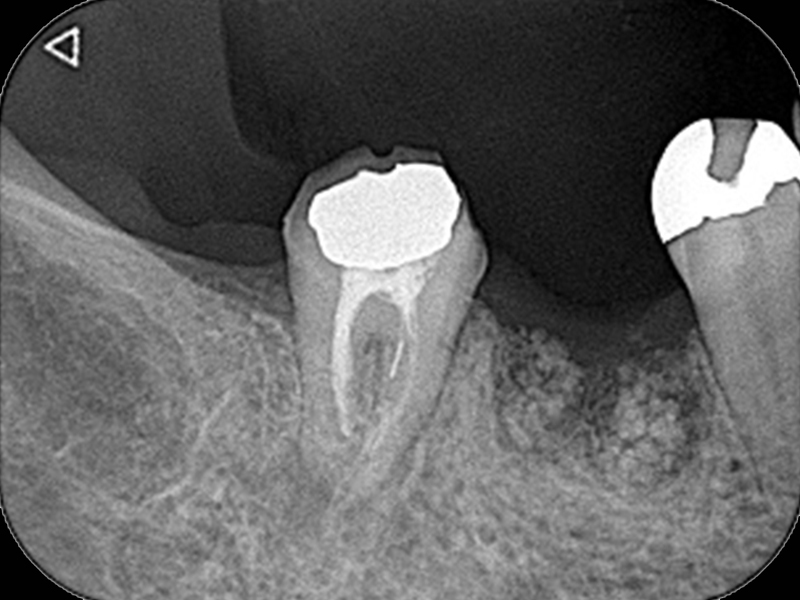

紹介され来院していただいた時には痛みはなかったので、まずは根の治療をする前にむし歯を完全に取り除いた後、ラバーダム防湿がきちんとできるように囲いを作製してから根の治療をはじめていきました。2回目の治療で症状ないのを確認してから根の中に最終的なつめ物をしていきました。

| 所見 | 左上第一大臼歯 最低限の根の治療のみ行っている 歯の横の部分にまだむし歯が残っている状態 |

| 年齢・性別 | 42歳 女性 |

| 主訴 | 何もしなくても歯が痛い |

| 治療内容 | 大臼歯抜髄 (紹介医に痛みを取る最低限の処置をしていただいてから紹介) |

| 治療費 | 176,000円 (税込) |

| 治療期間 | 2回(診療時間60~90分/回) |

| リスク・副作用 | 再発の場合は、外科処置で対応の可能性 |